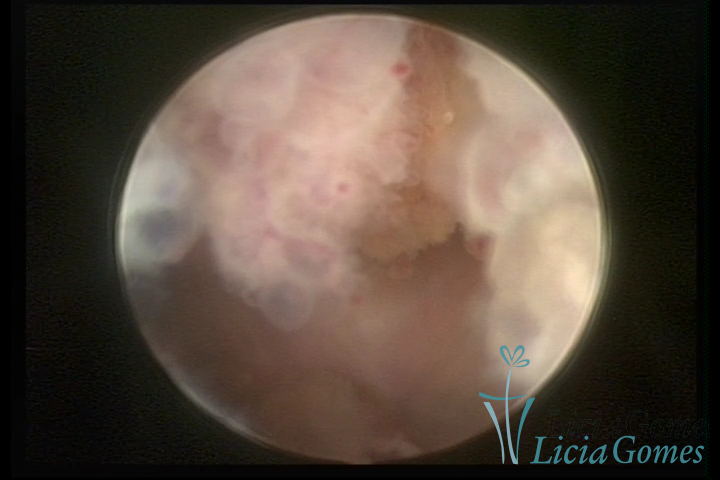

Este pode apresentar uma gama variável de aspectos macroscópicos, com aspecto pseudopolipoide; lembrando tecido cerebroide ou com reação deciduoide;a vascularização superficial é mais evidente e com vasos em formatos de saca-rolha ou espirais visualizando também a vascularização com atípias, com aumento do calibre dos vasos superficiais, pode ser encontrado também tecido em necrose, poderá haver um pequenos dendritos (papilomatoso).